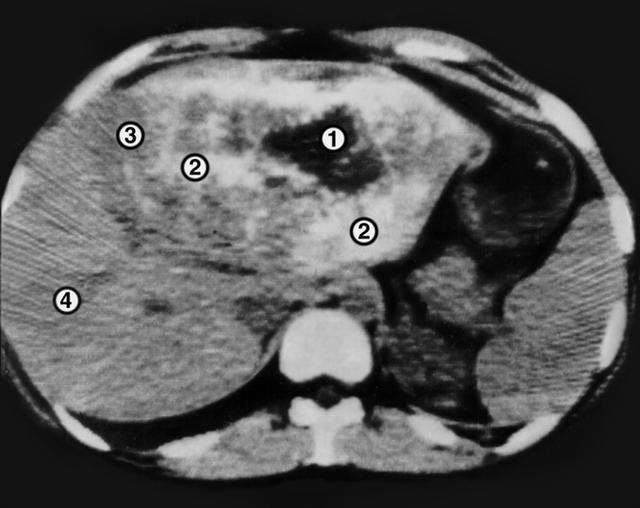

Рис. 4. Компьютерная томограмма при альвеолярном эхинококкозе печени: 1 — полость распада, 2 ткань паразитарного узла, 3 граница зоны поражения, 4 ткань печени.